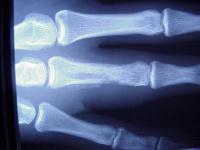

Radiographs show evidence of osteomyelitis with bone erosion and subperiosteal bone formation (arrows).